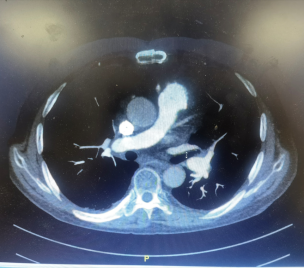

入院后,徐鸥主任第一时间与心外三病区张恒主任联系,对熊大爷的手术指征进行全面评估。于3月3日转入心外三病区后,先后进行了冠状动脉造影、先心病导管+造影,肺动脉增强CTA,心脏超声等一系列相关检查,提示主肺动脉、左右肺动脉干及双肺下叶肺动脉干管腔内多发充盈缺损影,左肺上叶、右肺中叶、下叶多发肺动脉分支官腔纤细、闭塞。经过肺血管与综合内科病区徐鸥主任和心外科病区王小啟主任经过多学科综合讨论下指定了详尽的手术方案,十余日的精心术前准备,于3月17日顺利进行了肺动脉内膜剥脱术,肺动脉血栓清除术:术中采用全身低温体外循环,期间行深低温停循环2min,使用剥离子仔细分离肺动脉内膜及机化血栓直至右侧肺叶动脉分叉处,并将血栓及内膜整块剥出。手术顺利,熊大爷于术后第4日状态平稳从SICU转回病房,氧分压(P02)从本次入院51.5mmHg升至出院时67.7mmHg,血氧浓度(SO2)吸氧后从85.4%升至92.6%,超声示肺动脉高压(重度)降至轻度肺动脉高压,于4月3日顺利出院。